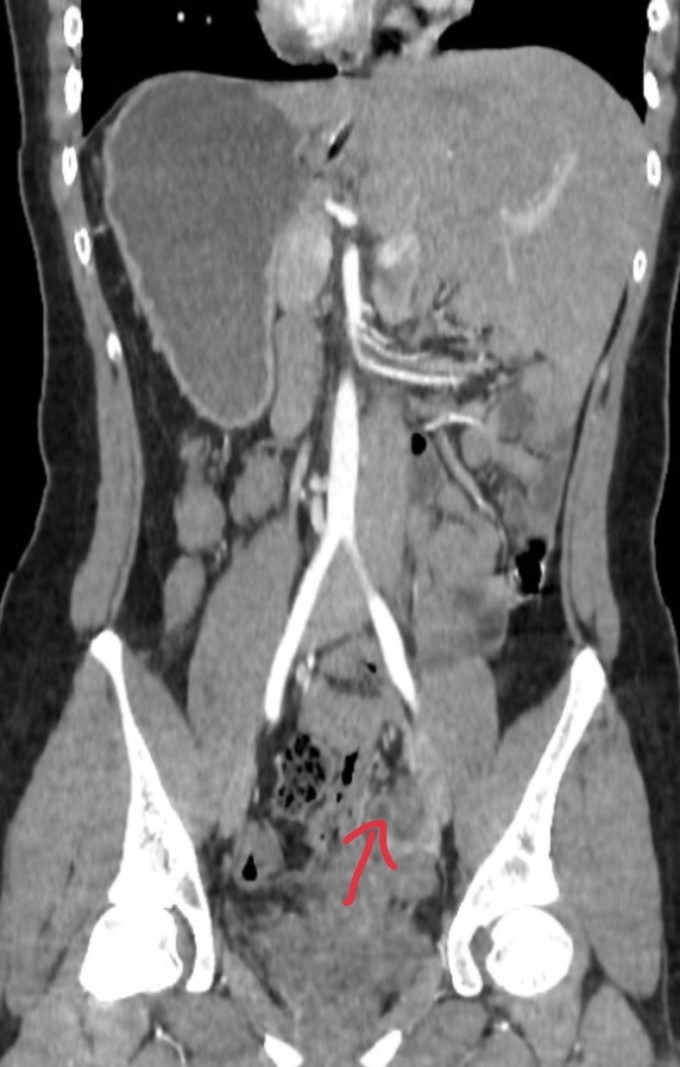

Qua khám lâm sàng và kết quả các xét nghiệm, siêu âm bụng, chụp CT ổ bụng, các bác sĩ đã xác định người bệnh bị viêm phúc mạc khu trú do ruột thừa mủ trên nền người bệnh bị đảo ngược phủ tạng hiếm gặp.

Theo đó, trái tim và dạ dày của người bệnh nằm bên phải, còn gan và ruột thừa lại nằm bên trái, trái ngược hoàn toàn so với bình thường.